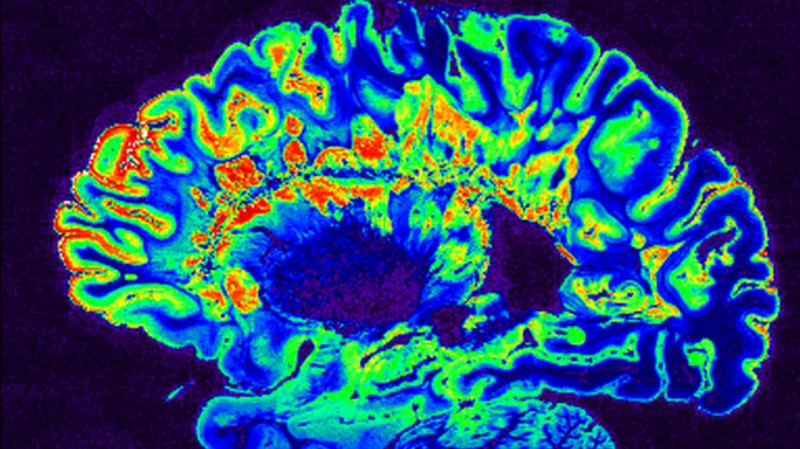

@ct24.ceskatelevize.cz · 13.3.2026

Čeští vědci vedení Milanem Němým z ČVUT využívají umělou inteligenci k odhalování drobných problémů v mozku, které mohou předcházet rozvoji duševních onemocnění, jako je Alzheimerova choroba. Pomocí moderních metod magnetické rezonance (MRI) se zaměřují na zachycení jemných změn v mozkových strukturách a jejich propojení, které nelze snadno vidět. #UměláInteligence #VýzkumMozku #AlzheimerovaChoroba

Čeští vědci využívají AI k hledání "překlepů" v mozku